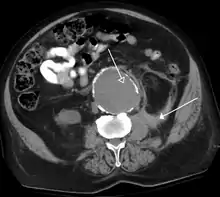

Медична візуалізація — це методика і процес створення візуальних зображень внутрішніх органів з метою проведення клінічного аналізу і медичного втручання. Медична візуалізація використовується для огляду внутрішніх структур тіла людини, а також для діагностики і лікування хвороб. Крім того, за допомогою цієї методики створюють базу даних нормальної анатомії і фізіології, яка дозволить виявляти аномалії. У медицині також виконують візуалізацію видалених органів і тканин, однак такі процедури зазвичай відносять до патології, а не до медичної візуалізації.

Як дисципліна в найширшому сенсі, медична візуалізація є розділом біологічної візуалізації, й до неї належать радіологія, у якій зображення формується за допомогою рентгенівських променів (радіографія), МРТ, медична акустика, чи ультразвукова діагностика, ендоскопія, еластографія, тактильна візуалізація, термографія, медична фотографія й такі методики функціональної візуалізації ядерної медицини, як позитрон-емісійна томографія.